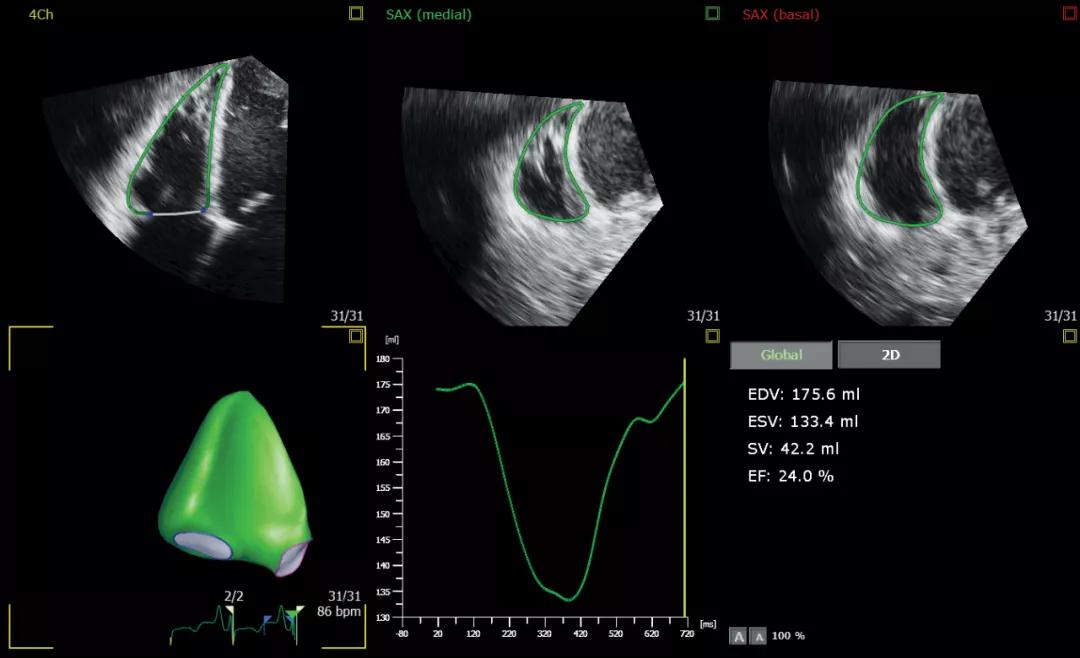

全新的心功能定量技术也对介入医生有着很大的帮助:“这台新的超声系统融入了AI元素,不仅可以帮助医生加深理解心脏结构和毗邻关系,还能快速评估心功能各项指标,如左心室、左心房等心腔的功能。以往医生对患者病情判断偏重于对心脏腔室关系的评估,现在新增了心脏功能的评估,将使得治疗更精准。”

AITT 3D Auto RV分析右室